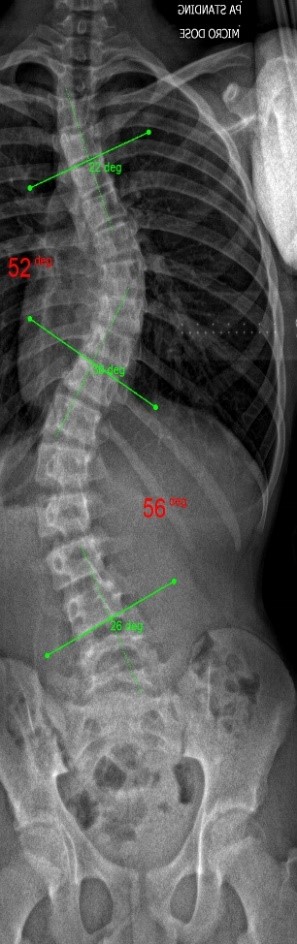

The clinical test results show that the SCN800 series is highly consistent with the X-ray, with a linear correlation of 0.94, similar results have also been published in SCI articles (Lee TT, Lai KK, Cheng JC, Castelein RM, Lam TP, Zheng YP. 3D ultrasound imaging provides reliable angle measurement with validity comparable to X-ray in patients with adolescent idiopathic scoliosis. Journal of Orthopaedic Translation. 29:51-59, 2021).

In our clinical trials and studies, we measured two angles to facilitate comparison. X-rays can actually show 3 to 4 angles, some in the neck and bottom area. Ultrasound images can also measure angles near the neck like an X-ray.

The following images compare 5 ultrasound and X-ray clinical measurement examples: